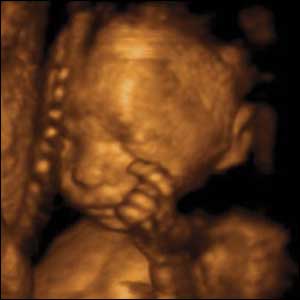

22 weeks gestation, 21 cm from crown to rump.

3 of 10

At 22 weeks gestation babies are capable of fine hand and finger movements. In a short space of time this baby scratches, rubs and pats his cheek before doing the same to his nose.